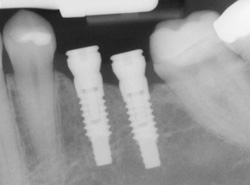

Implants

If you have missing teeth, it is crucial to replace them. Without all your teeth, chewing and eating can destabilize your bite and cause you discomfort. When teeth are missing, your mouth can shift and even cause your face to look older. Implants are a great way to replace your missing teeth, and if properly maintained, can last a lifetime!

An implant is a new tooth made of metal and porcelain that looks just like your natural tooth. It’s composed of two main parts: One part is the titanium implant body that takes the place of the missing root, and the second part is the tooth-colored crown that is cemented on top of the implant. With periodontal treatment, you can smile confidently knowing that no one will ever suspect you have a replacement tooth.

In addition to tooth replacement, implants may be used to anchor dentures, especially lower dentures that tend to shift when you talk or chew. For patients with removable partial dentures, implants can replace missing teeth so that you have a more natural-looking smile.